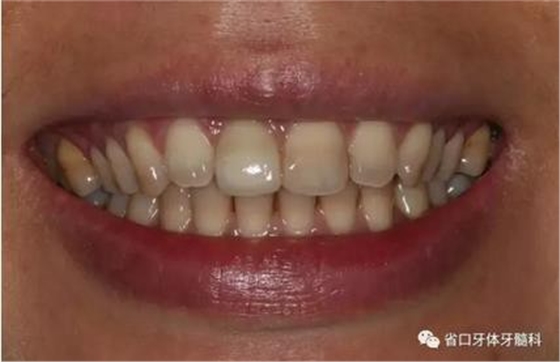

1.?病例簡介 43歲女性患者,主拆:右上前牙松動不適數(shù)日要求修復(fù)。現(xiàn)病史:患者數(shù)年前右上前牙因“齲壞”于外院行根管治療(具體不詳),數(shù)日前牙冠松動不適,現(xiàn)覺影響咀嚼及美觀,遂來我院要求進(jìn)一步診治。否認(rèn)高血壓、心臟病等重大疾病,否認(rèn)結(jié)核、肝炎等傳染病史,否認(rèn)手 術(shù)、輸血史等,未發(fā)現(xiàn)藥物過敏。無吸煙習(xí)慣。臨床檢查:口外觀顏面基 本對稱,皮膚無紅腫破潰,顳下頜關(guān)節(jié)區(qū)無彈響、雜音、壓痛,開口度約 37mm,開口型“↓”,頜下、刻下和頸部未及腫大淋巴結(jié)。中位笑線??趦?nèi)檢查,口腔衛(wèi)生可,色素(+),BOP(-),PD=2mm,上頜右側(cè)中切 牙冠部變色,冠根折斷至齦下3mm,叩不適,松動Ⅱ°~Ⅲ°。牙齦稍紅, 齦緣水平及齦乳頭高度可,屬于中厚齦生物型,附著齦寬度約5mm,唇系帶附著可。上頜右側(cè)中切牙缺牙間隙與對側(cè)同名牙一致,約>7mm,修復(fù)空 間良好。與對頜牙覆合覆蓋正常。MCT檢查示上頜右側(cè)中切牙冠根折斷至骨 下,根管內(nèi)見充填物,根充不全,根尖見陰影,大小約3mm×3mm。牙槽窩根方可用骨量可,唇側(cè)骨壁完整,冠方骨壁厚度約1mm。

圖1 術(shù)前口內(nèi)照

圖2 術(shù)前口內(nèi)照

圖3 術(shù)前口內(nèi)照